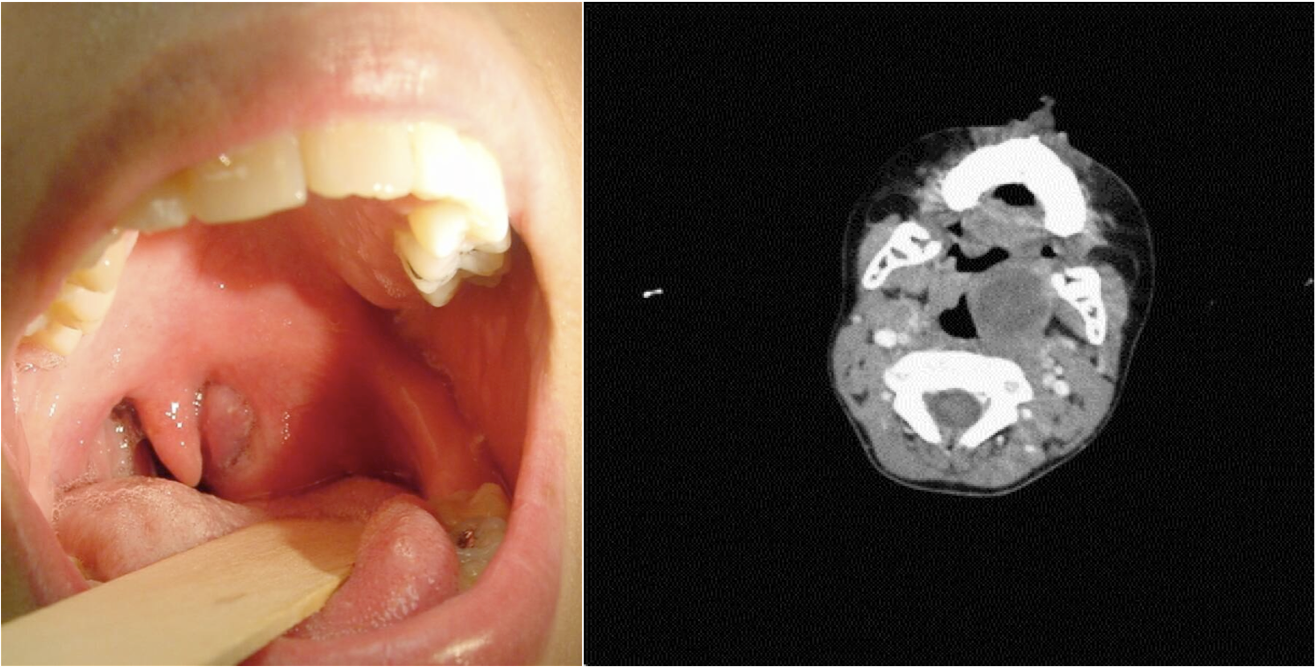

Peritonsillar abscess (Quinsy)

An abscess between the tonsil capsule and the adjacent lateral pharyngeal wall common deep infection in late childhood

- Clinical diagnosis

- CT scan